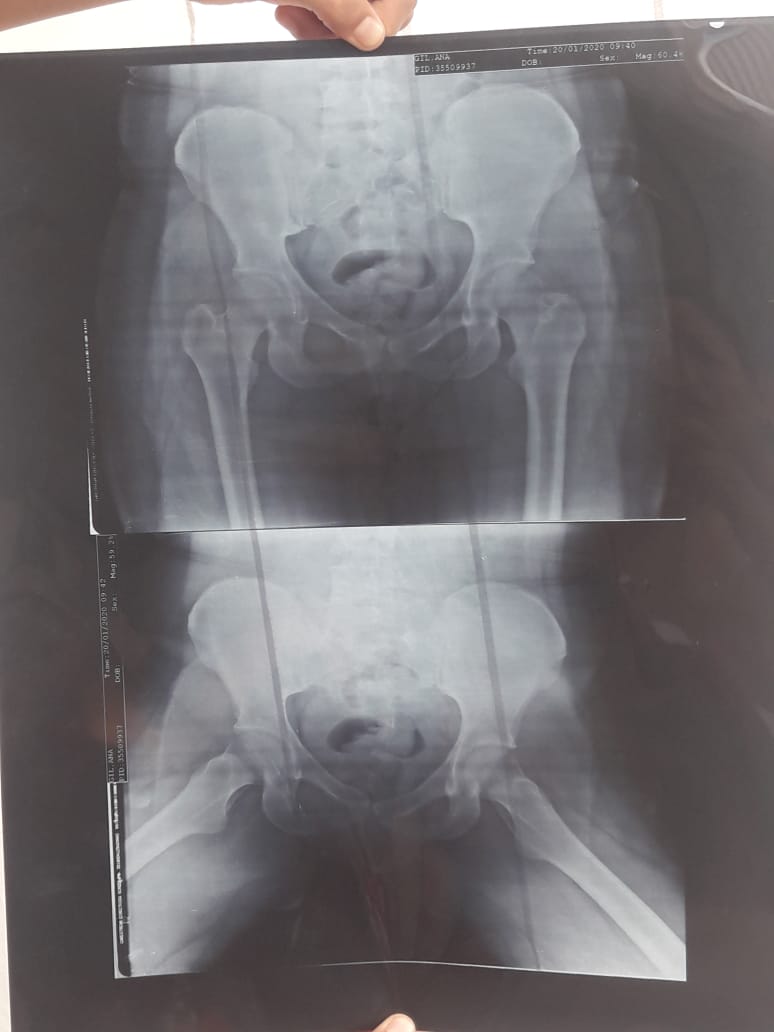

Una de las radiografías de pelvis que se realizó Ana María.

La joven oriunda de Rivadavia contó que la obra social que tiene (Incluir Salud) no le cubre la cirugía en el exterior porque el hospital donde debe realizarse la intervención está fuera de la Red Pública Nacional de Salud. “Fui a Salud Pública y me dijeron que me podían ayudar con la mitad, pero yo no tengo de donde más sacar dinero, apelo a la solidaridad de la gente o de alguna empresa que pueda ayudarme a tener una vida, es difícil pasar los días sufriendo pensando que vas a terminar en una silla de ruedas sabiendo que la cura está, existe y está en México”, comentó Ana María mientras sostenía en sus manos la última radiografía de pelvis.